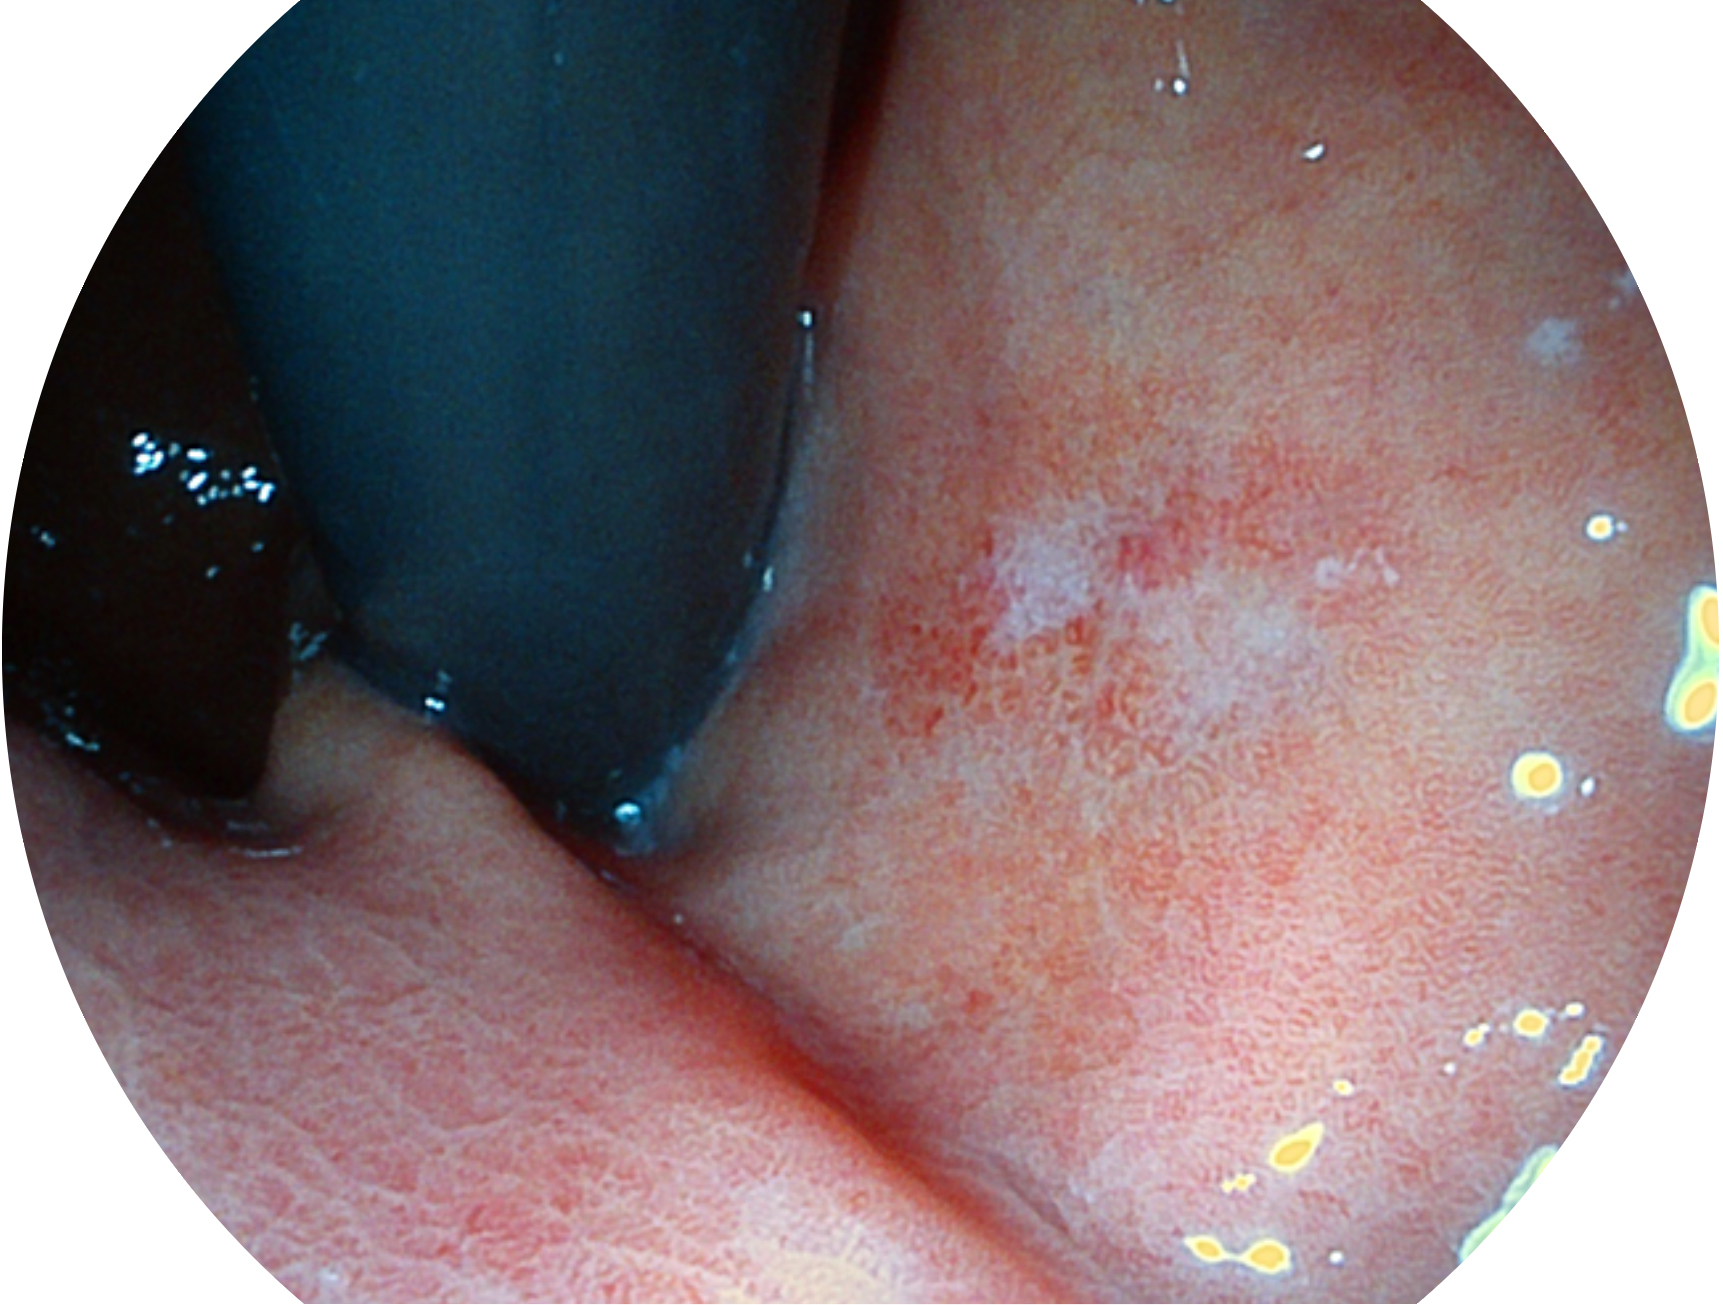

乐玩lewin国际新开发的内镜染色技术,主要是基于多波长LED 光源的开发,VLS-55Q 四波长LED 光源是由四个不同颜色的LED光按照相应照明模式所规定的特定发光比例进行合束后形成,合束后形成的照明光的光谱由红光、绿光、蓝光及蓝紫光这四个不同的波段范围构成。具有更高光谱自由度,通过光谱比例的控制,实现了聚谱成像技术,英文全称为“Spectral Focused Imaging, SFI”,缩写为“SFI”和光电复合染色成像技术,英文全称为“Versatile Intelligent Staining Technology, VIST”,缩写为“VIST”。